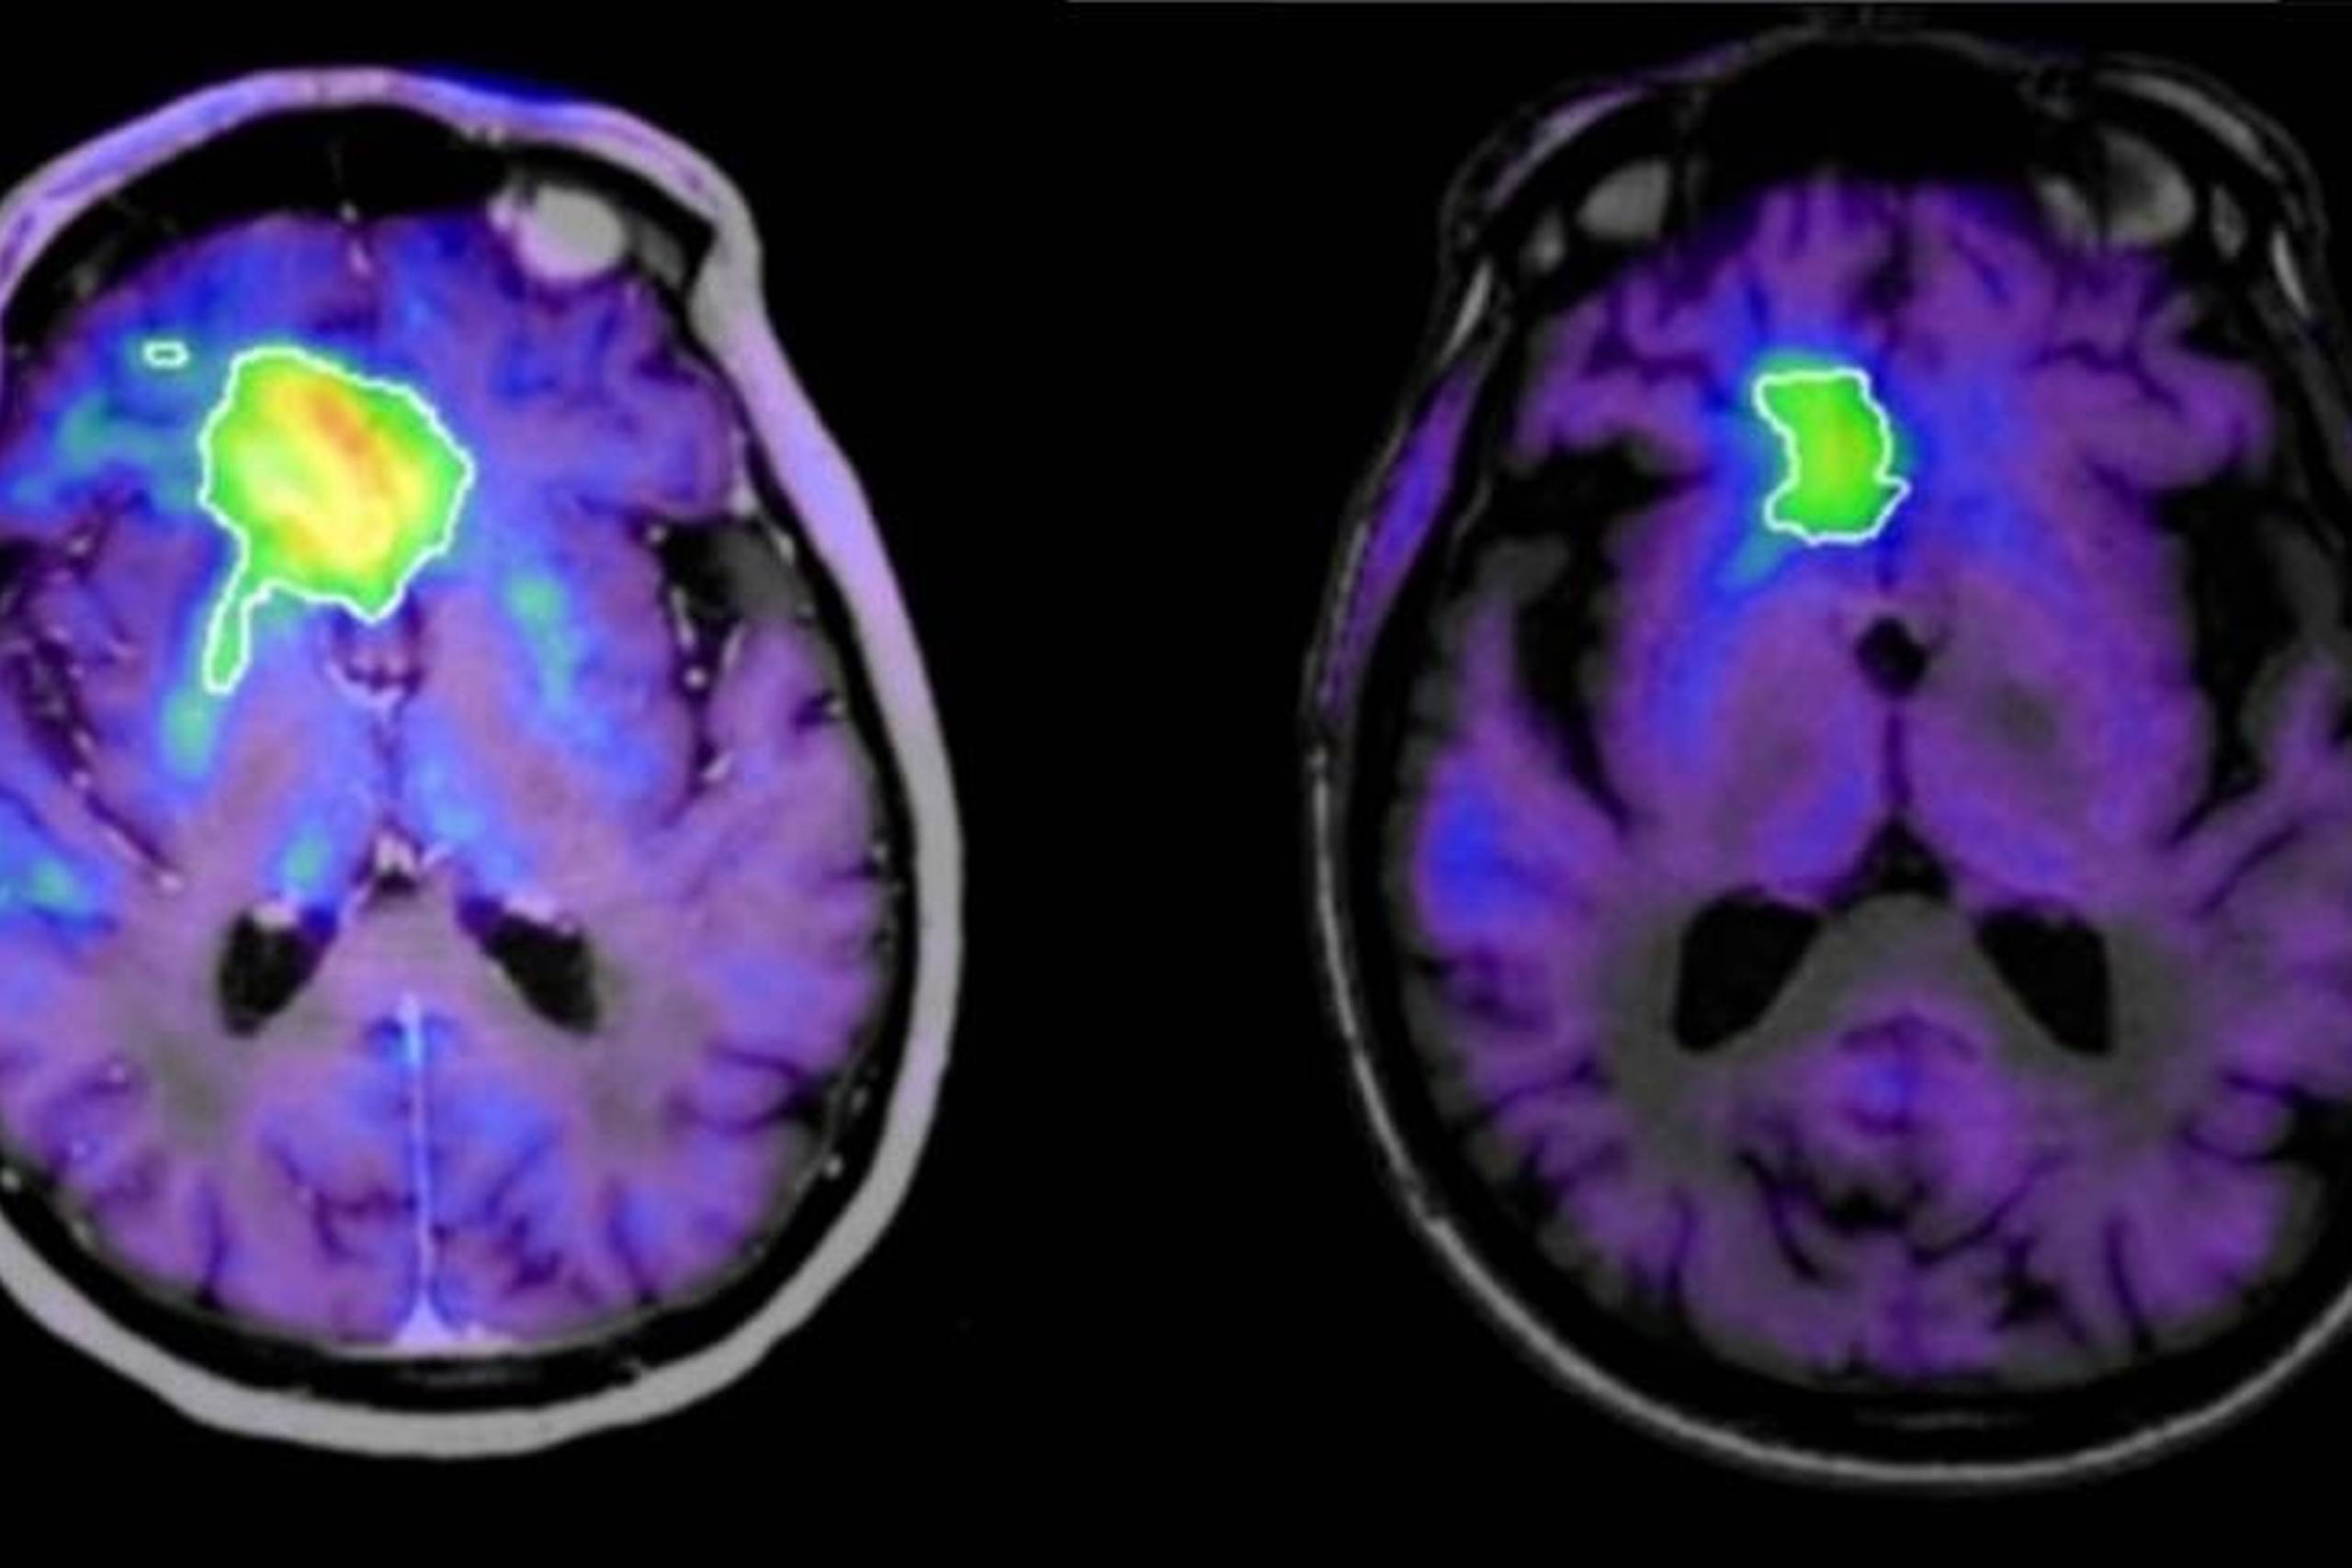

31. mar. 2020InternationalHvorfor reagerer vi så forskelligt på ekstrem stress? Franske forskere har undersøgt hjernen på terrorofre